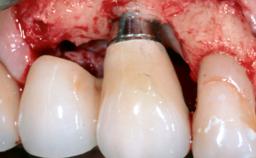

A 72-year-old female patient was referred to the specialist clinic with signs of peri-implantitis associated with implant 14. Two implants (sites 14 and 15) had been in function for three years. The patient was in good general health and was not taking any medication. She was a former smoker (12–15 cigarettes a day for 50 years) but had ceased smoking two years prior to implant placement. Her periodontal condition was stable, with no probing depths above 5 mm and a full-mouth plaque score (FMPS) of 35%.